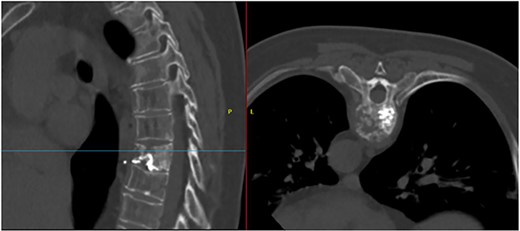

Imaging tests revealed a T7 pathologic fracture (Figs 1 and 2). First, X-ray-assisted percutaneous biopsy and kyphoplasty were inconclusive. Second, CT-assisted percutaneous biopsy and kyphoplasty revealed trabecular infiltration by hypercellular hyaline cartilage with cellular atypia, without relevant mitotic activity. Histological diagnosis of a Grade I chondrosarcoma was then established and the patient was directed to our clinic.

Alteration in the morphology and signal of the T7 vertebral body that presents a fracture with 30% loss of height and dorsal protrusion of posterior wall, with a left and epidural soft tissue component, the signal change extends to the left pedicle and part of the posterior arch. The right lateral margin of T8 vertebral body presents a hypointense signal on T1 and markedly hyperintense on STIR that indicates the presence of osseous edema. These findings suggest T7 pathological fracture and bone edema in the left T8 pedicle.

After PET scan, metastatic disease was discarded. Complete spine magnetic resonance and thoraco-abdominopelvic CT indicated the location on T7 vertebral body, with both end plates broken and causing a leakage to intervertebral disks. Moreover, an intensity change in the left pedicle of T8 was found, which could not be discarded as tumoral (Figs 2 and 3). Surgical resection been the only possible treatment, the patient was appointed to undergo total en bloc vertebrectomy of T7 and T8 and partial of caudal T6, following the technique described by Tomita et al. [1]

T7 pathological fracture with breakage of both superior and inferior end plates. Cement from the performed kyphoplasty is present, with leakage into the anterior paravertebral space.